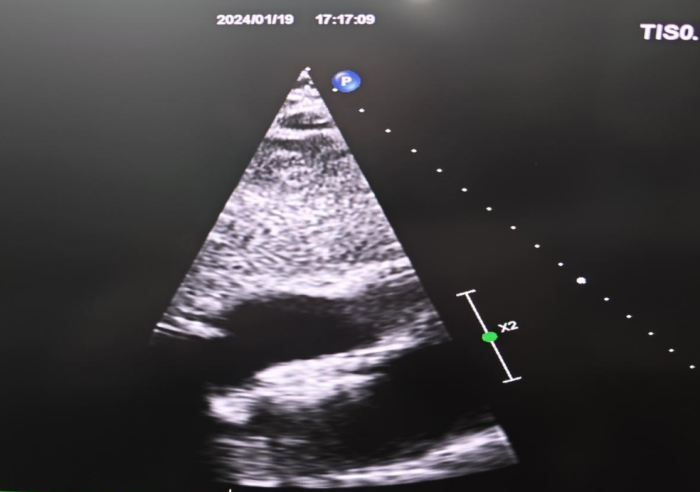

封堵器释放,贴壁良好

此次手术从导丝穿刺房间隔到封堵器释放,全程在彩超引导下进行。封堵器释放后,彩超提示封堵器形态良好,行牵拉试验示封堵器结实固定于房间隔处后,完美释放卵圆孔封堵器,术后头晕明显改善,第2天好转出院。